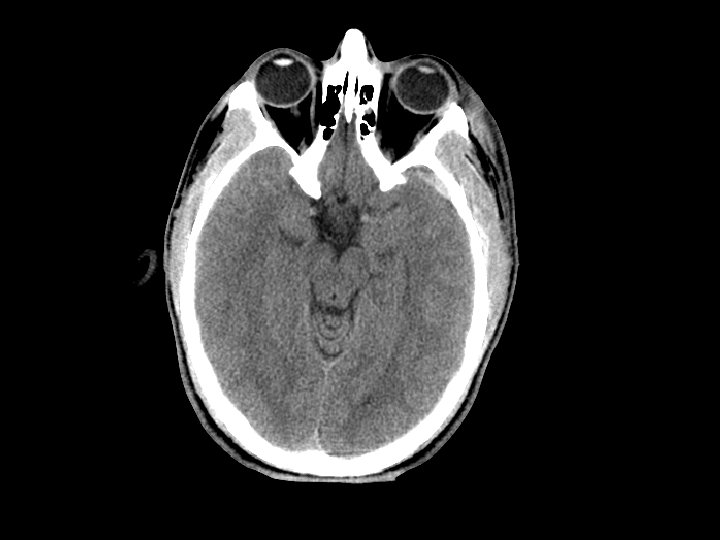

Subarrachnoid Hemorrhage (SAH) • SAH and contusion are most common injuries on CT after blunt trauma • CT: blood in the sulci and basal cisterns • Often associated with intracranial hematomas • Must consider that the SAH caused the trauma (spontaneous bleed and then fall) • Complications: – Arterial vasospasm: 2 -3 days after injury

Diffuse Axonal Injury (DAI) • Shearing and rotational forces disrupt the axonal network • Mechanism: rapid acceleration/deceleration injury • Imaging – Not well visualized by CT – MRI can better define the extent of injury • No specific therapy • Likely results in the persistent neurologic deficits in patients with normal CT scans but substantial injury